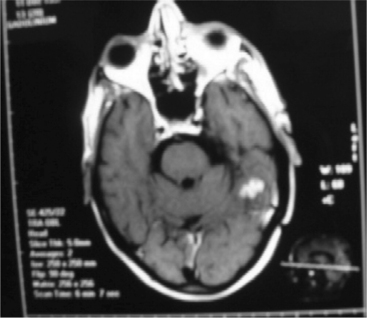

Tuberculous Meningitis.: Tuberculous meningitis is an infection by Mycobacterium tuberculosis, which enters the body by inhalation.15,42 CNS involvement includes abscess or spinal cord disease. A computed tomography (CT) image of a tuberculoma is seen in Fig. 29-2. Tuberculous brain abscesses may produce mass effect and edema. CSF may demonstrate formation of multiple cysts with lymphocytes and an elevated protein. Infected bacilli enter the subarachnoid space to cause diffuse meningitis.28

Lumbar puncture is the only absolute means of substantiating a diagnosis of meningitis. The viruses causing viral meningitis can be isolated in CSF and include enteroviruses, lymphocytic choriomeningitis, and herpes simplex virus. Lumbar puncture reveals mononuclear cells in the hundreds, a normal glucose level, a mild increase in protein, and absence of bacterial organisms (see the section on Laboratory Values in Chapter 40). Radiographs are taken to rule out fracture, sinusitis, and mastoiditis. A CT scan or magnetic resonance imaging (MRI) will reveal evidence of brain abscess or infarction that may be responsible for the symptoms. Fig. 29-2 shows evidence of abnormal MRI with tuberculous meningitis.